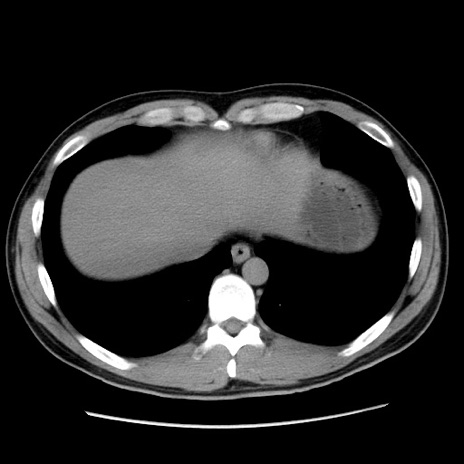

症例36(横断像)

【症例】20歳代 男性

【主訴】心窩部痛

【現病歴】今朝より上腹部痛あり。一旦軽快していたが再度出現したため救急要請。昨日夕に白身の魚を含む刺身を食べた。

【身体所見】BP 136/89mmHg、HR 74/min、BT 37.0℃、腹部:膨満、軟、心窩部に圧痛あり。反跳痛なし、筋性防御なし、腸雑音やや亢進あり。

【データ】WBC 17700、CRP 0.48